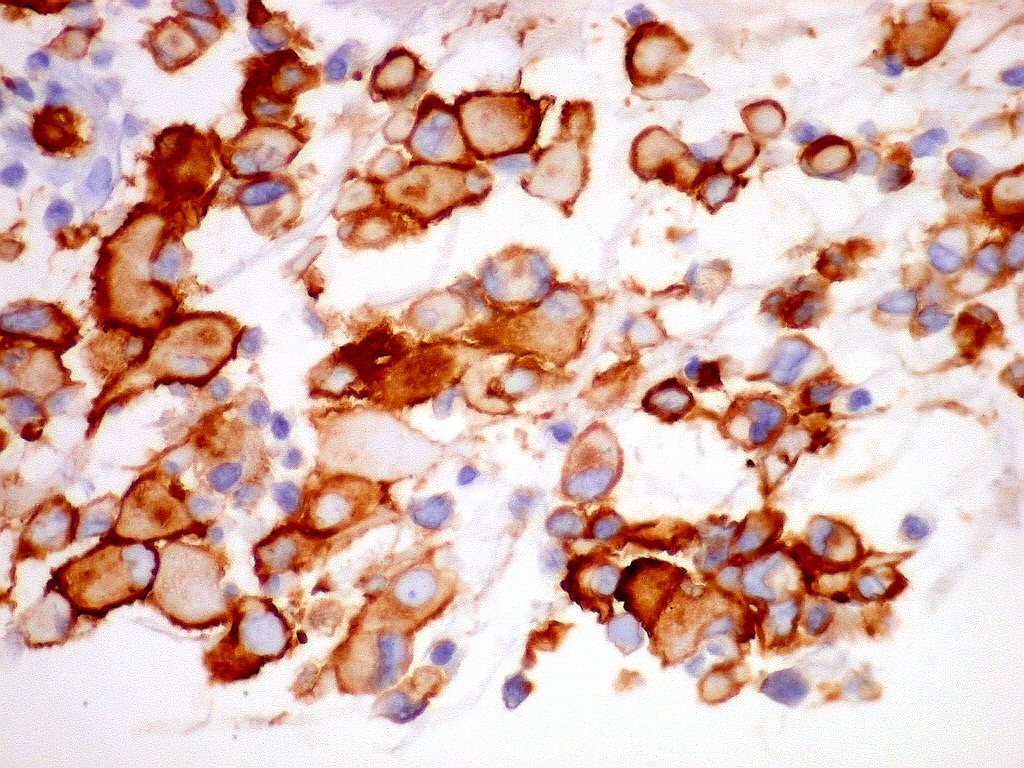

MAP2.   Microtubular associated protein,  marcador de diferenciação  neuronal. Universalmente positivo nas células deste ATRT.  Folículo linfóide  negativo (controle  interno).  Marcação é citoplasmática, na periferia do citoplasma.  Corpúsculo rabdóide negativo.  Para mais sobre MAP2, clique.